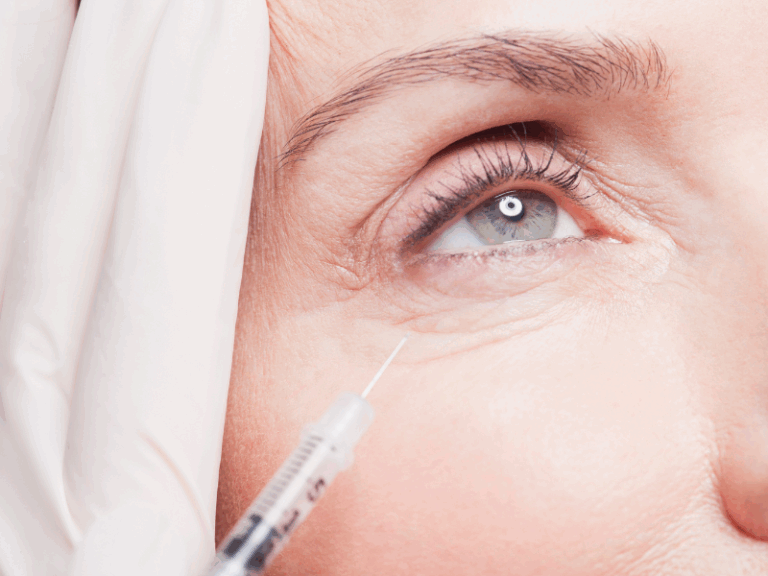

במהלך הטיפול מזריק הרופא חומרי מילוי סמיכים אשר מיועדים לפיסול האף, בעיקר חומצה היאלורונית או חומרים על בסיס קלציום. הרופא מזריק לעומק את החומר, בדרך כלל לאורך הקו המרכזי של האף, בעדינות ובאיטיות, לרוב באמצעות קנולה – זאת על מנת להימנע מפגיעה וחדירת חומר המילוי לאחד מהעורקים הרבים באזור זה של הפנים. הרופא מעצב ומפסל את חומר המילוי במבנה האף באופן כזה שיהיה בטיחותי ושייטיב עם פניו של המטופל ויביא אותם למראה סימטרי, מעוצב וטבעי.

כמו בכל הליך רפואי ישנו סיכוי לתופעות לוואי כגון: נפיחות, אדמומיות וכאב קל באזור הרקות. אולם, אלו חולפים כעבור ימים בודדים והתוצאה שמתקבלת הינה טבעית ואסתטית מאין כמותה. כאשר הטיפול מבוצע על ידי רופא אסתטיקה מנוסה בתחום, מרבית המטופלים עוברים את ההליך ללא כל תופעות לוואי.